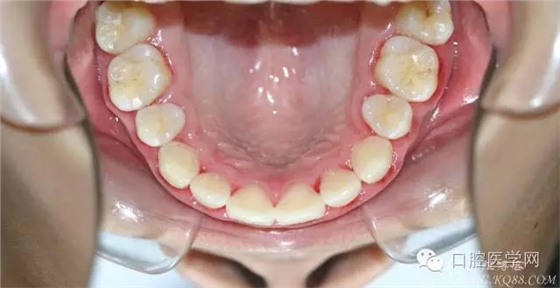

正畸查:替牙合。第一恒磨牙中性合。上牙弓尖圓型下牙弓方圓型。前牙覆合3度覆蓋7.5mm。下前牙咬到上舌側(cè)牙齦。上頜擁擠4.0mm,下頜擁擠

3.0mm。上頜稍前突下頜后縮,上下唇前突,上前牙覆蓋下唇,下唇外翻。面下三分之一過短,頦唇溝明顯,開唇露齒,頦饜窩明顯。顳下頜關(guān)節(jié)開閉口無彈響,無壓痛,開口型開口度正常。

正畸前照片: